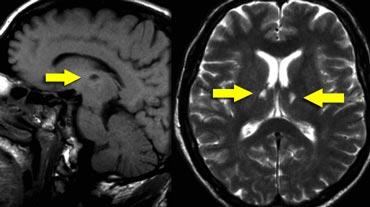

Bên trái là hình ảnh CT và MRI tại mức mép trước (mũi tên xanh).

Trên CT, ghi nhận một vùng giảm tỷ trọng ở bán cầu phải, vùng này có tín hiệu tương đồng với dịch não tủy trên chuỗi xung T2W và FLAIR, đây là đặc điểm điển hình của khoang Virchow-Robin giãn rộng.